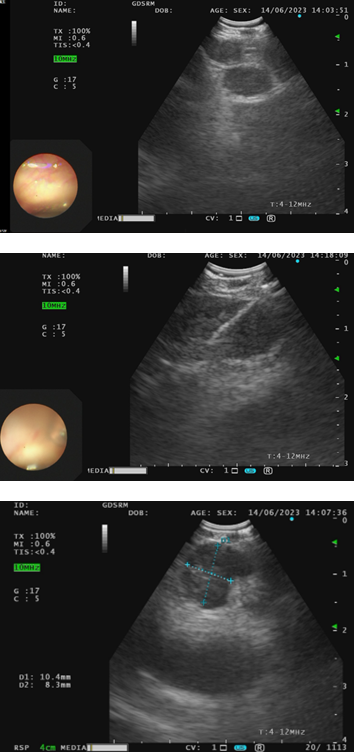

至2022年12月,患者CEA及CA15-3持续升高;2023年6月进一步检查提示疾病全面复发,DFS约60个月。PET/CT显示左肺上叶下舌段结节、区域多发肿大淋巴结以及胸腰椎多发骨质破坏,并伴糖代谢增高,提示肺、淋巴结及骨转移。

随后行超声支气管镜(EBUS)取材,转移灶仍表现为Luminal B1型,其中11L淋巴结ER 3+ 99%、PR 1+ 5%、HER2 2+且HER2基因无扩增、Ki-67约10%+;4R淋巴结ER 3+ 95%、PR 1+ 10%、HER2 1+且HER2基因无扩增、Ki-67约12%+。这提示患者虽已进入晚期阶段,但肿瘤仍保留较明确的激素受体驱动特征。